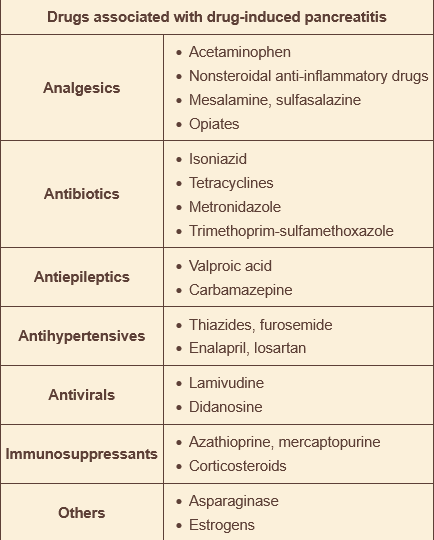

______ is a hypertension drug associated with pancreatitits

hydrochlorothiazide